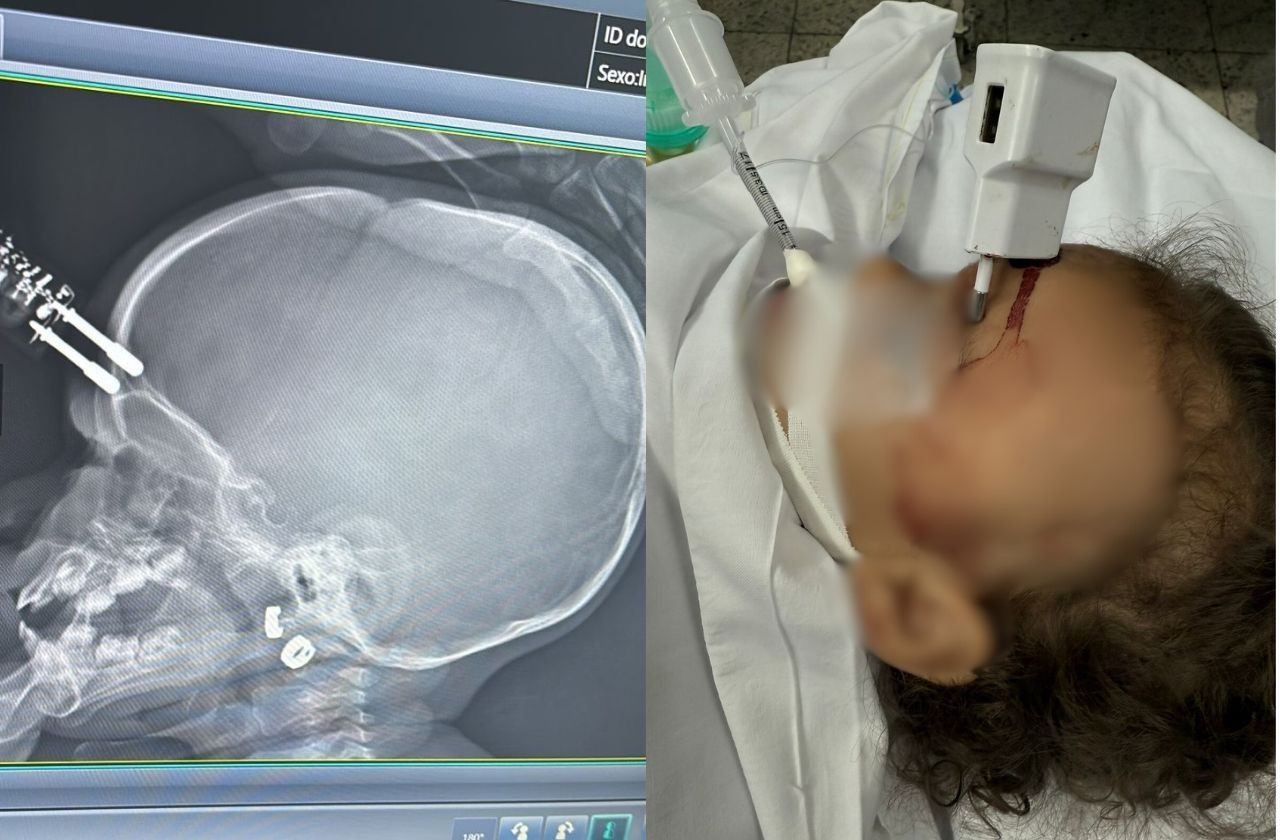

Uma menina de 1 ano e quatro meses sofreu um grave acidente doméstico em Divinópolis, na região oeste de Minas Gerais, ao cair da cama e atingir a testa em um carregador de celular que estava no chão.

O objeto ficou cravado na cabeça da criança, que precisou ser submetida a cirurgia de emergência. De acordo com a mãe, ela foi ao banheiro e deixou a filha sozinha na cama por alguns instantes. Logo depois, ouviu o choro da menina e a encontrou no chão, com os pinos do carregador cravados na testa.

Ela acionou o Samu, que realizou o atendimento e encaminhou as duas para a UPA. Segundo o neurologista Bruno Castro, que atendeu o caso, o carregador chegou a perfurar o crânio da menina, provocando uma fratura.

Ela foi inicialmente atendida na Unidade de Pronto Atendimento (UPA) de Divinópolis e, em seguida, transferida para o Hospital São João de Deus, onde passou por cirurgia imediata para retirada do objeto, correção da lesão e contenção de um pequeno sangramento.

Após o procedimento, a criança foi levada ao Centro de Terapia Intensiva (CTI), onde permaneceu por 36 horas. Ela passou por tomografia de controle e apresentou boa evolução clínica.